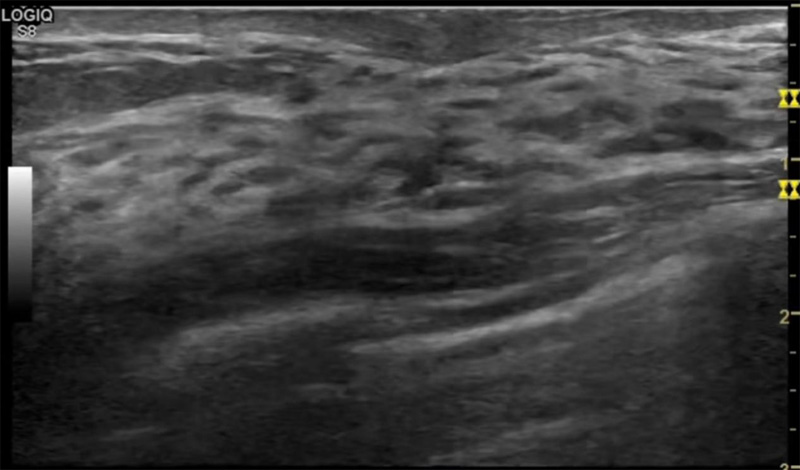

乳房脹痛,觸摸疼痛,手摸起來感覺有腫塊。這個是什么問題呢?醫(yī)生診斷一般是乳腺增生。那么在乳腺超聲設備檢查后,報告單卻顯示雙乳未見明顯占位性病變。乳腺增生是很多女性,特別是育齡期女性都有的經(jīng)歷、到底乳腺增生癥狀有哪些?會給我們帶來怎樣的影響呢?乳腺增生不是腫瘤跟炎癥。乳腺組織增生及退行性變跟內(nèi)分泌功能紊亂有關系。正常的生理改變。還有乳腺病,良性乳腺結構不良等名稱。

乳腺增生有什么癥狀,病因?比較典型的就是乳房疼痛,特別是經(jīng)前癥狀比較重,經(jīng)后就有所緩解。有時候還能碰到乳房硬塊。根據(jù)經(jīng)期的變化而變化硬度大小都有變。乳腺在內(nèi)分泌激素,伴隨月經(jīng)周期有增生問題。內(nèi)分泌激素代謝失衡,雌激素水平增高,出現(xiàn)乳腺組織增生過度,增生組織不退的情況下,就會有乳腺增生癥狀。這個不會增加乳腺癌的風險。所以不用緊張的。不過乳腺癌的病人都會有乳腺增生。所以乳腺增長有沒癥狀,都需要進行常規(guī)的體檢。